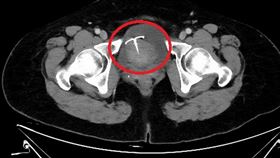

嚇!五旬婦腹痛不止 竟是避孕器穿透子宮

55歲的張女士日前因腹痛1個多月,本以為是腸胃症狀,...